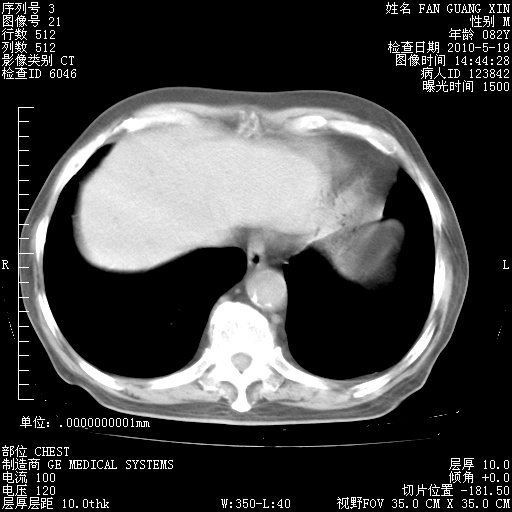

治疗3周后的肺部CT纵隔窗

从胸部影像学来看,的确有好转。至于目前为何发热不甚清楚?除了发热还有其他症状如有无喀痰,痰呈丝状吗?等等。尽量搜寻有无致发热其它可能原因?真菌?其它?如果的确无其他致发热的原因,考虑将甲强龙调至60-80mg bid/日。免疫全套基本无异常,考虑多系特发性肺间质纤维化